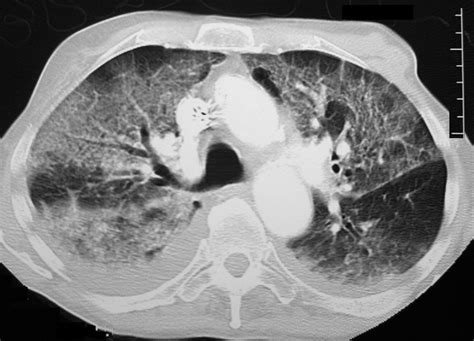

At its core, a ground glass opacity in lungs represents a partial filling of the air spaces (alveoli) in the lungs or a thickening of the interstitium (the framework of the lungs). While normal lung tissue is mostly air and appears black on a CT scan, GGOs look like a light cloud or a blurred, frosted glass pane. This phenomenon occurs because the density of the lung has increased slightly, but the air is not completely replaced by solid material, such as fluid, pus, blood, or fibrous tissue.

• Malignancy: In some cases, localized GGOs can represent early-stage lung adenocarcinoma or pre-cancerous conditions, particularly if they persist over time.

For those being monitored for persistent GGOs, the routine usually involves regular, scheduled imaging. The stability of the opacity—meaning it has not changed size or appearance over several scans—is usually considered a positive sign, suggesting a benign or indolent (slow-growing) process. If, however, the scan shows an increase in the size of the opacity or it becomes more solid, your pulmonologist will likely escalate the investigation to determine if medical or surgical intervention is required.